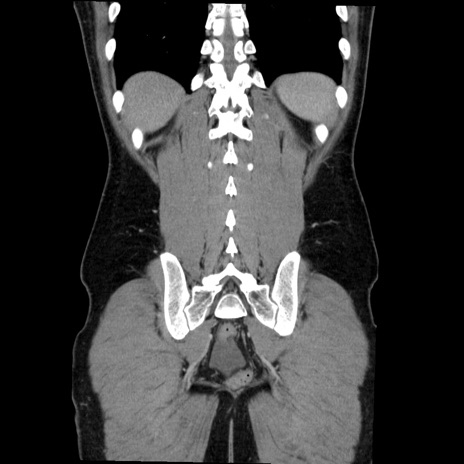

症例36(冠状断像)

【症例】20歳代 男性

【主訴】心窩部痛

【現病歴】今朝より上腹部痛あり。一旦軽快していたが再度出現したため救急要請。昨日夕に白身の魚を含む刺身を食べた。

【身体所見】BP 136/89mmHg、HR 74/min、BT 37.0℃、腹部:膨満、軟、心窩部に圧痛あり。反跳痛なし、筋性防御なし、腸雑音やや亢進あり。

【データ】WBC 17700、CRP 0.48